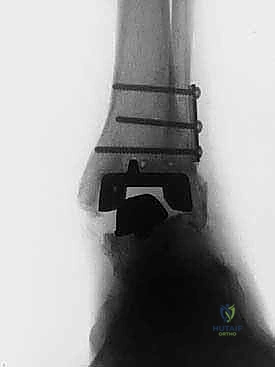

علاج هذه الكسور يتطلب مهارة فائقة من الدكتور محمد هطيف، حيث يتم استخدام تقنيات الجراحة الميكروسكوبية وتثبيت الكسور باستخدام صفائح معدنية دقيقة ومسامير (Locking Plates) دون المساس بثبات المفصل الصناعي، أو يتم دمج علاج الكسر ضمن عملية مراجعة المفصل الكلية إذا كان المفصل نفسه تالفاً.

يتم إدخال المفصل الجديد المخصص للمراجعة، والذي يحتوي غالباً على سيقان (Stems) تدخل عميقاً في عظمة الساق وعظمة الكاحل لضمان الثبات الميكانيكي. في حال وجود كسور في الكعب، يتم تثبيتها في هذه المرحلة.

الخطوة السادسة: الإغلاق التجميلي

يتم خياطة الأربطة والأنسجة الرخوة والجلد بطرق تجميلية دقيقة لتقليل الندبات وسرعة الالتئام، ثم توضع القدم في جبيرة خلفية واقية.